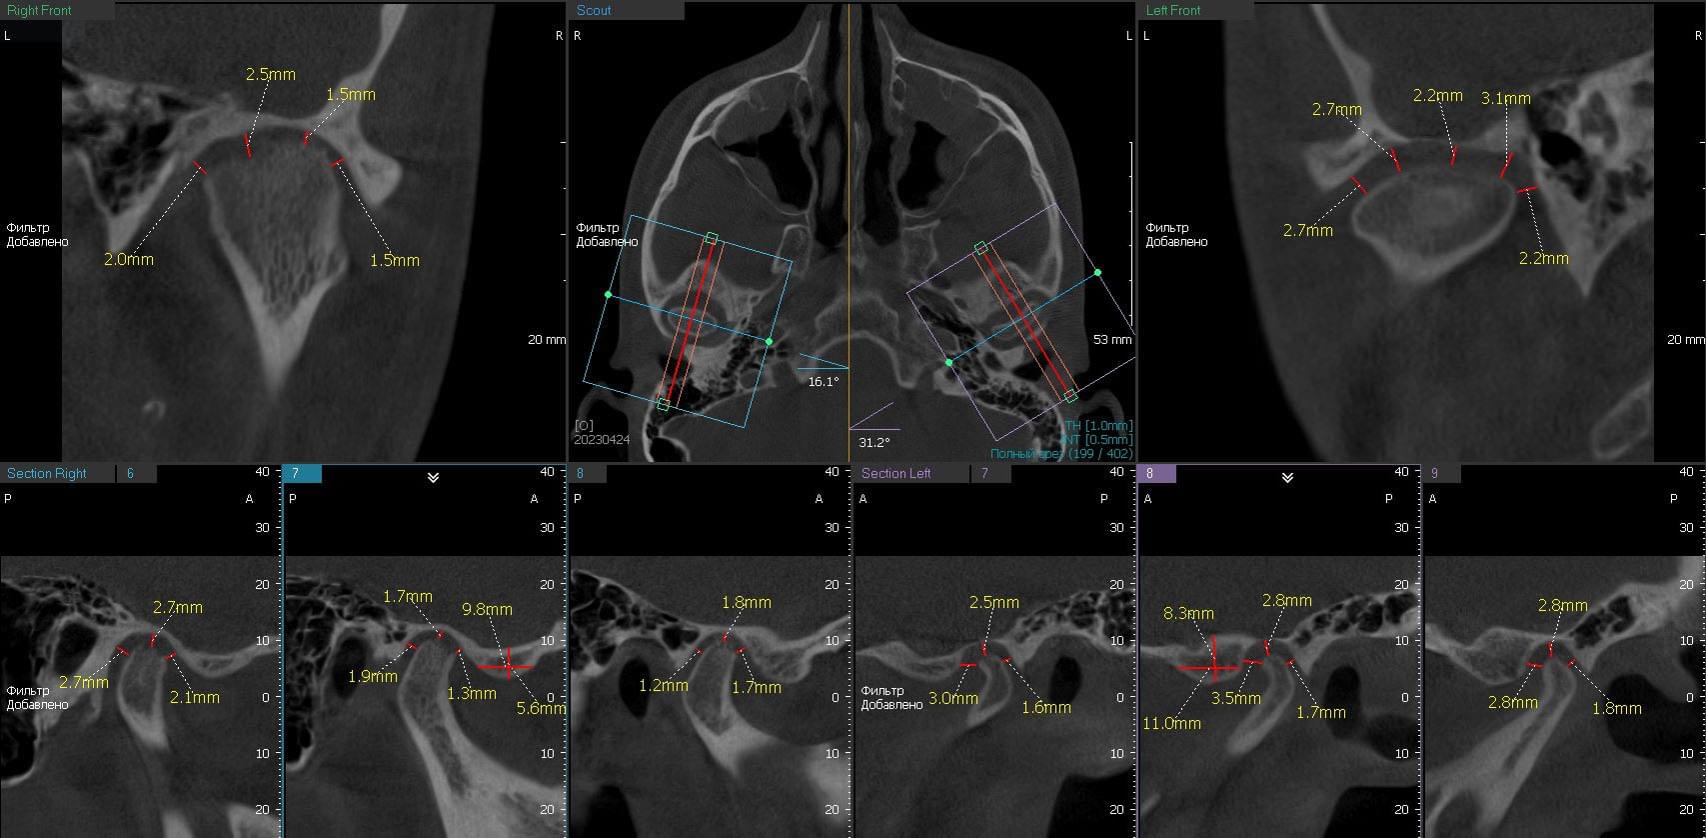

Дисфункція скронево-нижньощелепного суглобу

Якщо ви маєте сумніви щодо свого скронево-нижньощелепного суглобу, компанія MyRay Lab є вашим надійним партнером у діагностиці та визначенні причин цієї дисфункції. Ми спеціалізуємося на проведенні КТ-досліджень суглобів, черепа та навколишніх тканин, що дозволяє нам докладно оцінити структуру та функцію скронево-нижньощелепного суглобу.

Однією з головних переваг співпраці з MyRay Lab є наша високотехнологічна устаткування, що використовується в процесі КТ. Ми застосовуємо передові технології, які забезпечують зображення високої якості та дозволяють отримати детальну інформацію про стан суглобу. Наша компанія MyRay Lab використовує інноваційні методи та підходи, щоб допомогти нашим клієнтам у точному діагностуванні та розумінні проблем щодо їх скронево-нижньощелепного суглобу.

Здоров'я наших клієнтів є нашим пріоритетом, тому ми пропонуємо індивідуальний підхід до кожного пацієнта, що звертається до нас для діагностики дисфункції скронево-нижньощелепного суглобу. Наші досвідчені фахівці використовують комбінацію клінічного дослідження та КТ-сканування, щоб з'ясувати причини симптомів та розробити ефективний план лікування.